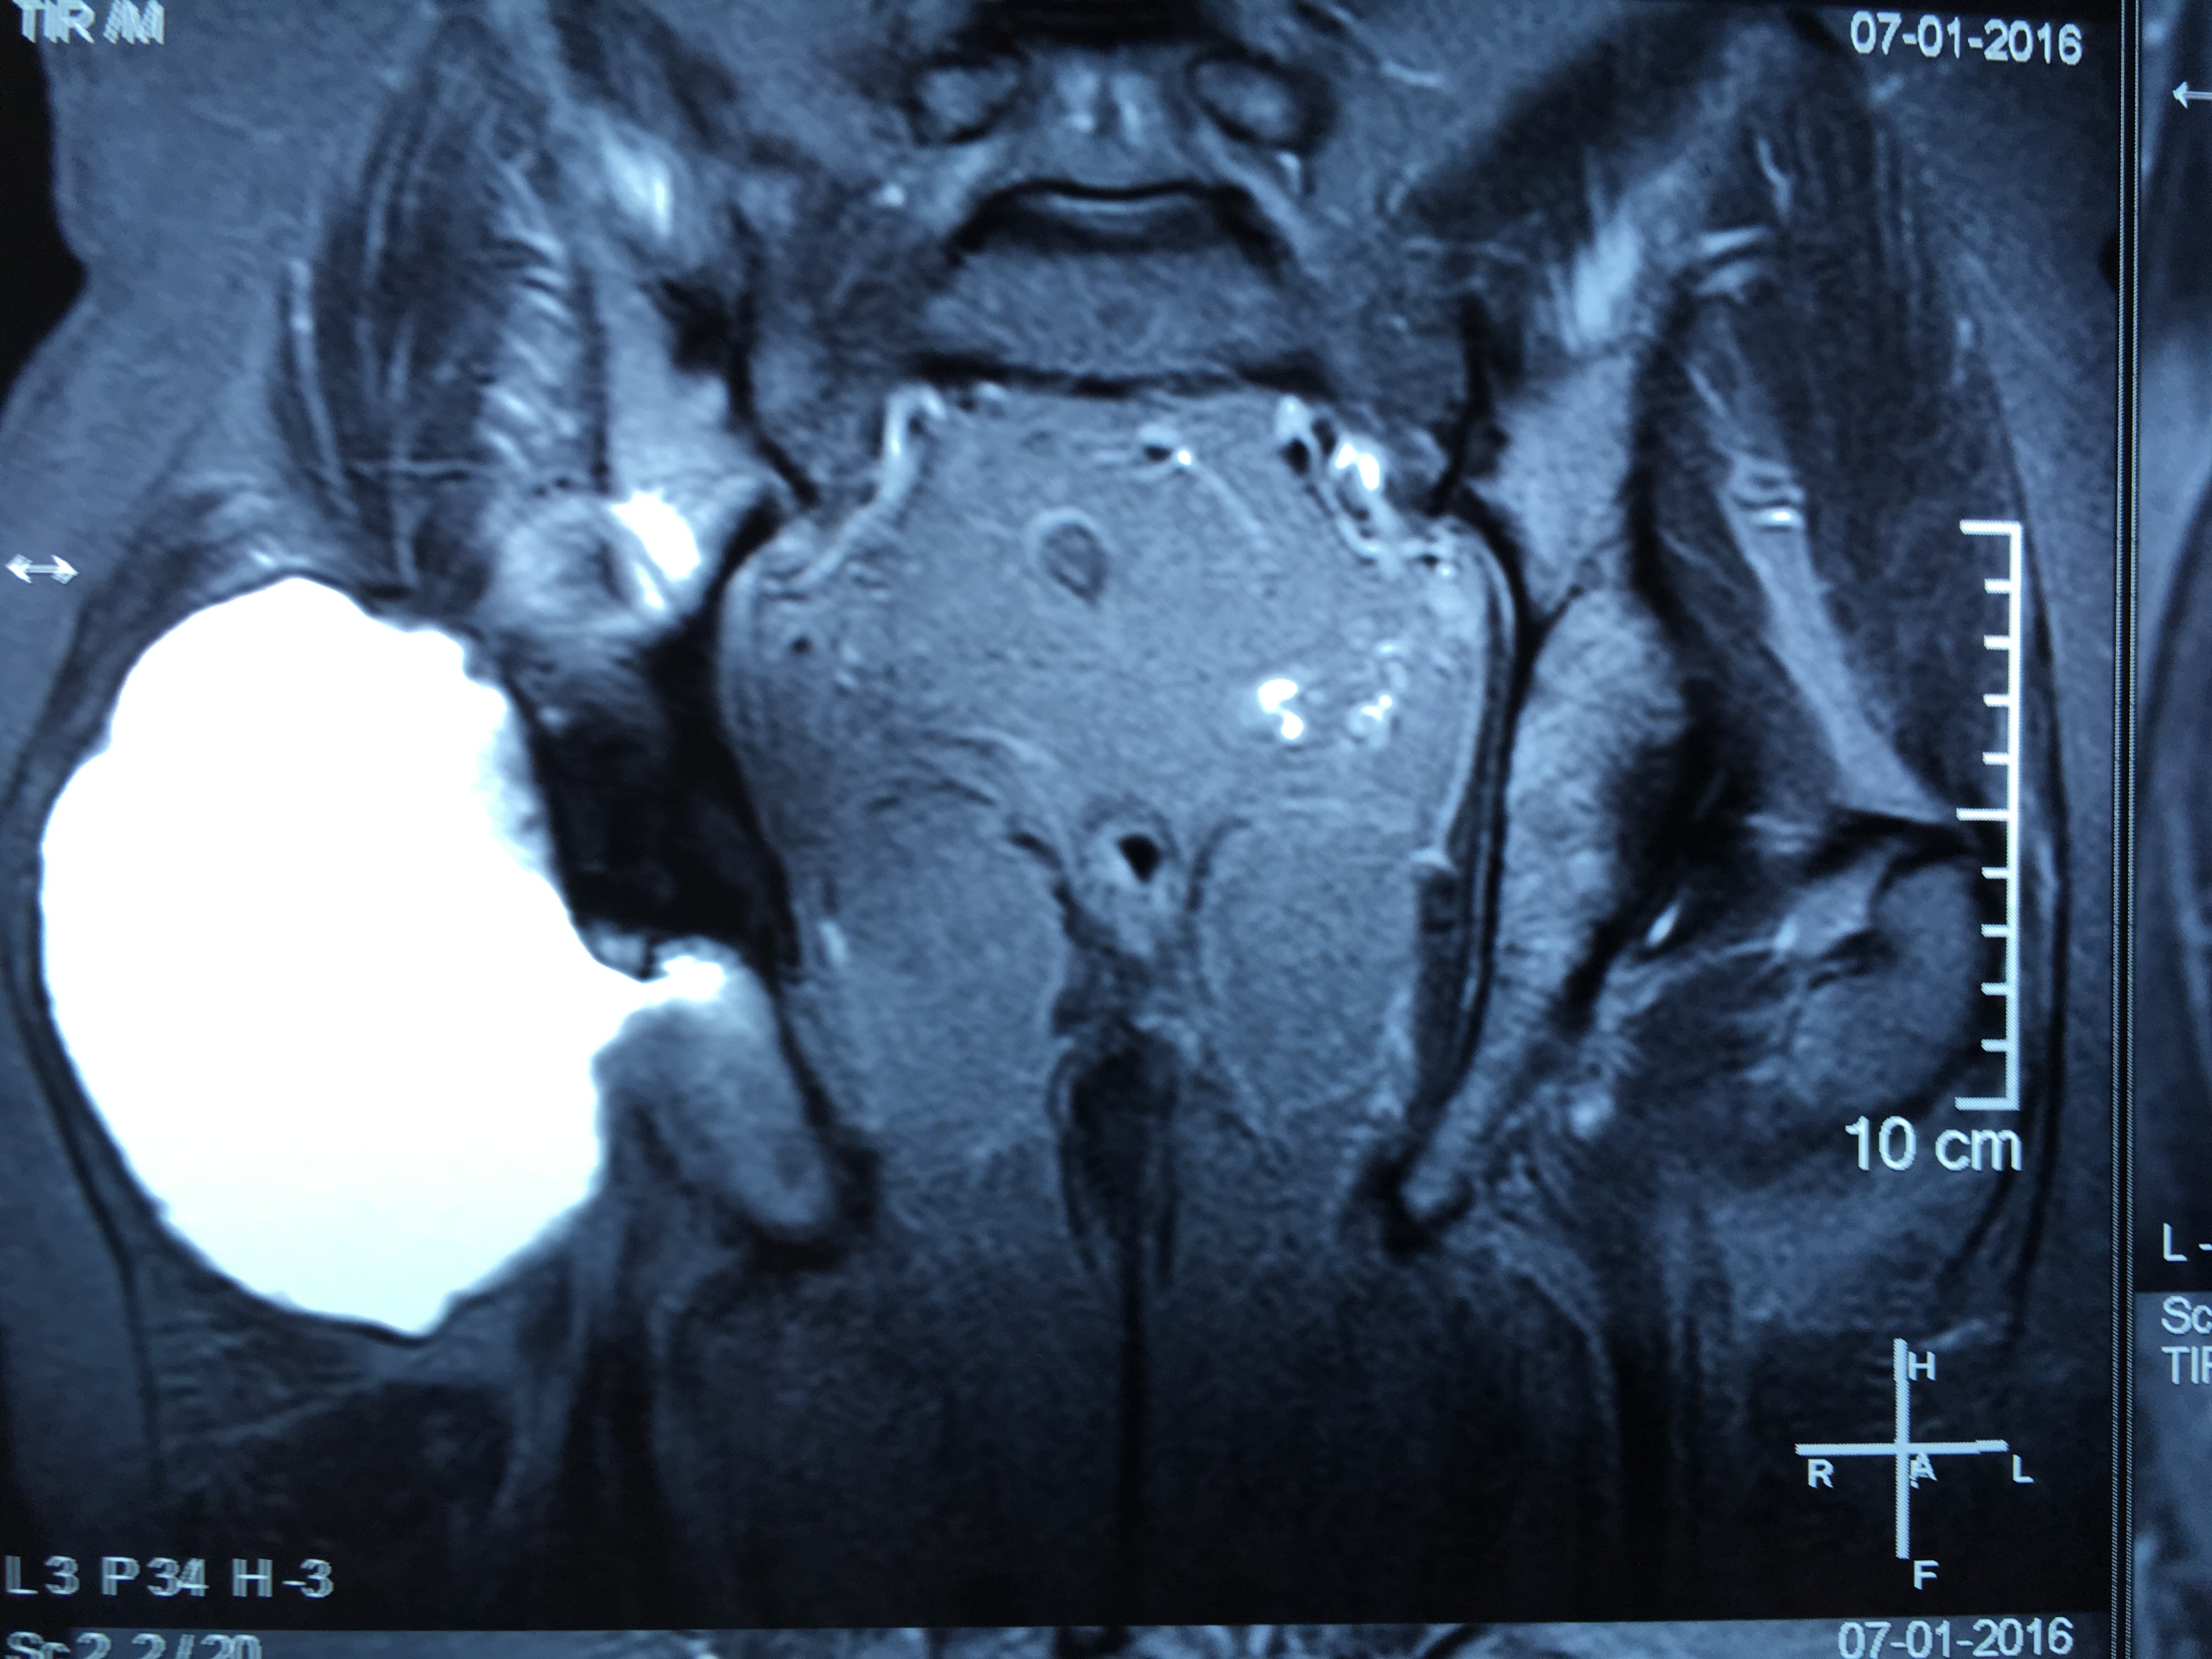

Cotilos de doble movilidad. Uso para la revisión femoral aislada de prótesis de cadera con fricción metal/metal con cabezas grandes. [Use of dual mobility acetabular cups for isolated femoral revision of metal on metal hip resurfacing arthroplasty using larger femoral heads]